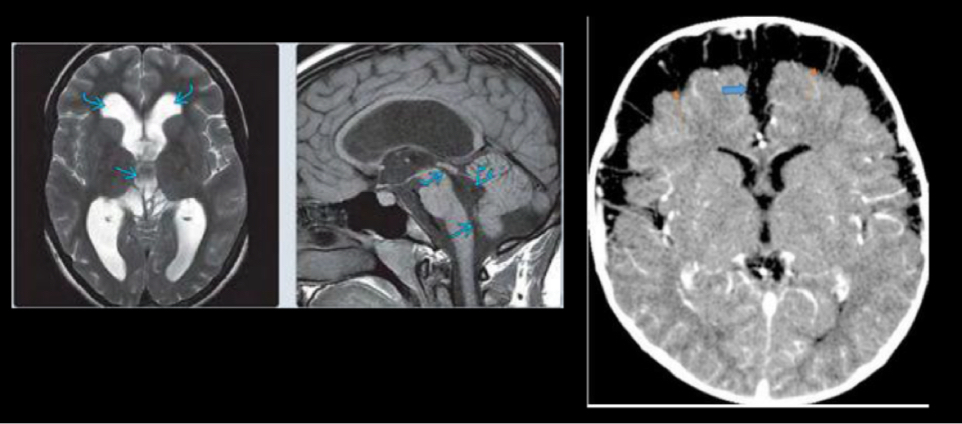

intraventricular

extra ventricular

23